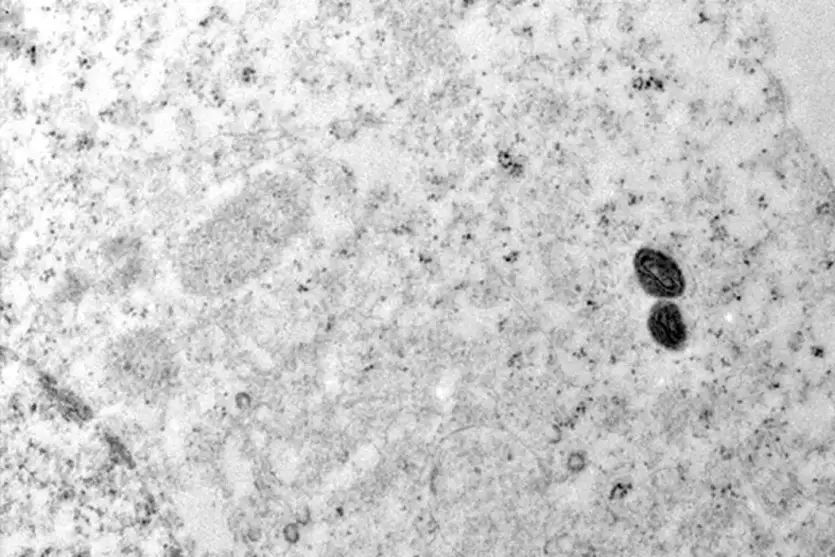

O Ministério da Saúde da Argentina descartou a suspeita de mpox em um tripulante de navio que saiu do Brasil e permanecia em quarentena no país vizinho. “Após exames laboratoriais, as autoridades de vigilância sanitária argentinas confirmaram que se tratava de varicela”, informou o Ministério da Saúde do Brasil, em nota.

No comunicado, o governo brasileiro reforçou que a variante 1b da mpox, que levou a Organização Mundial da Saúde (OMS) a declarar emergência em saúde pública de importância internacional, não está em circulação no Brasil. Em 2024, o país confirmou 791 casos da doença, mas todos da variante 2b, já conhecida.